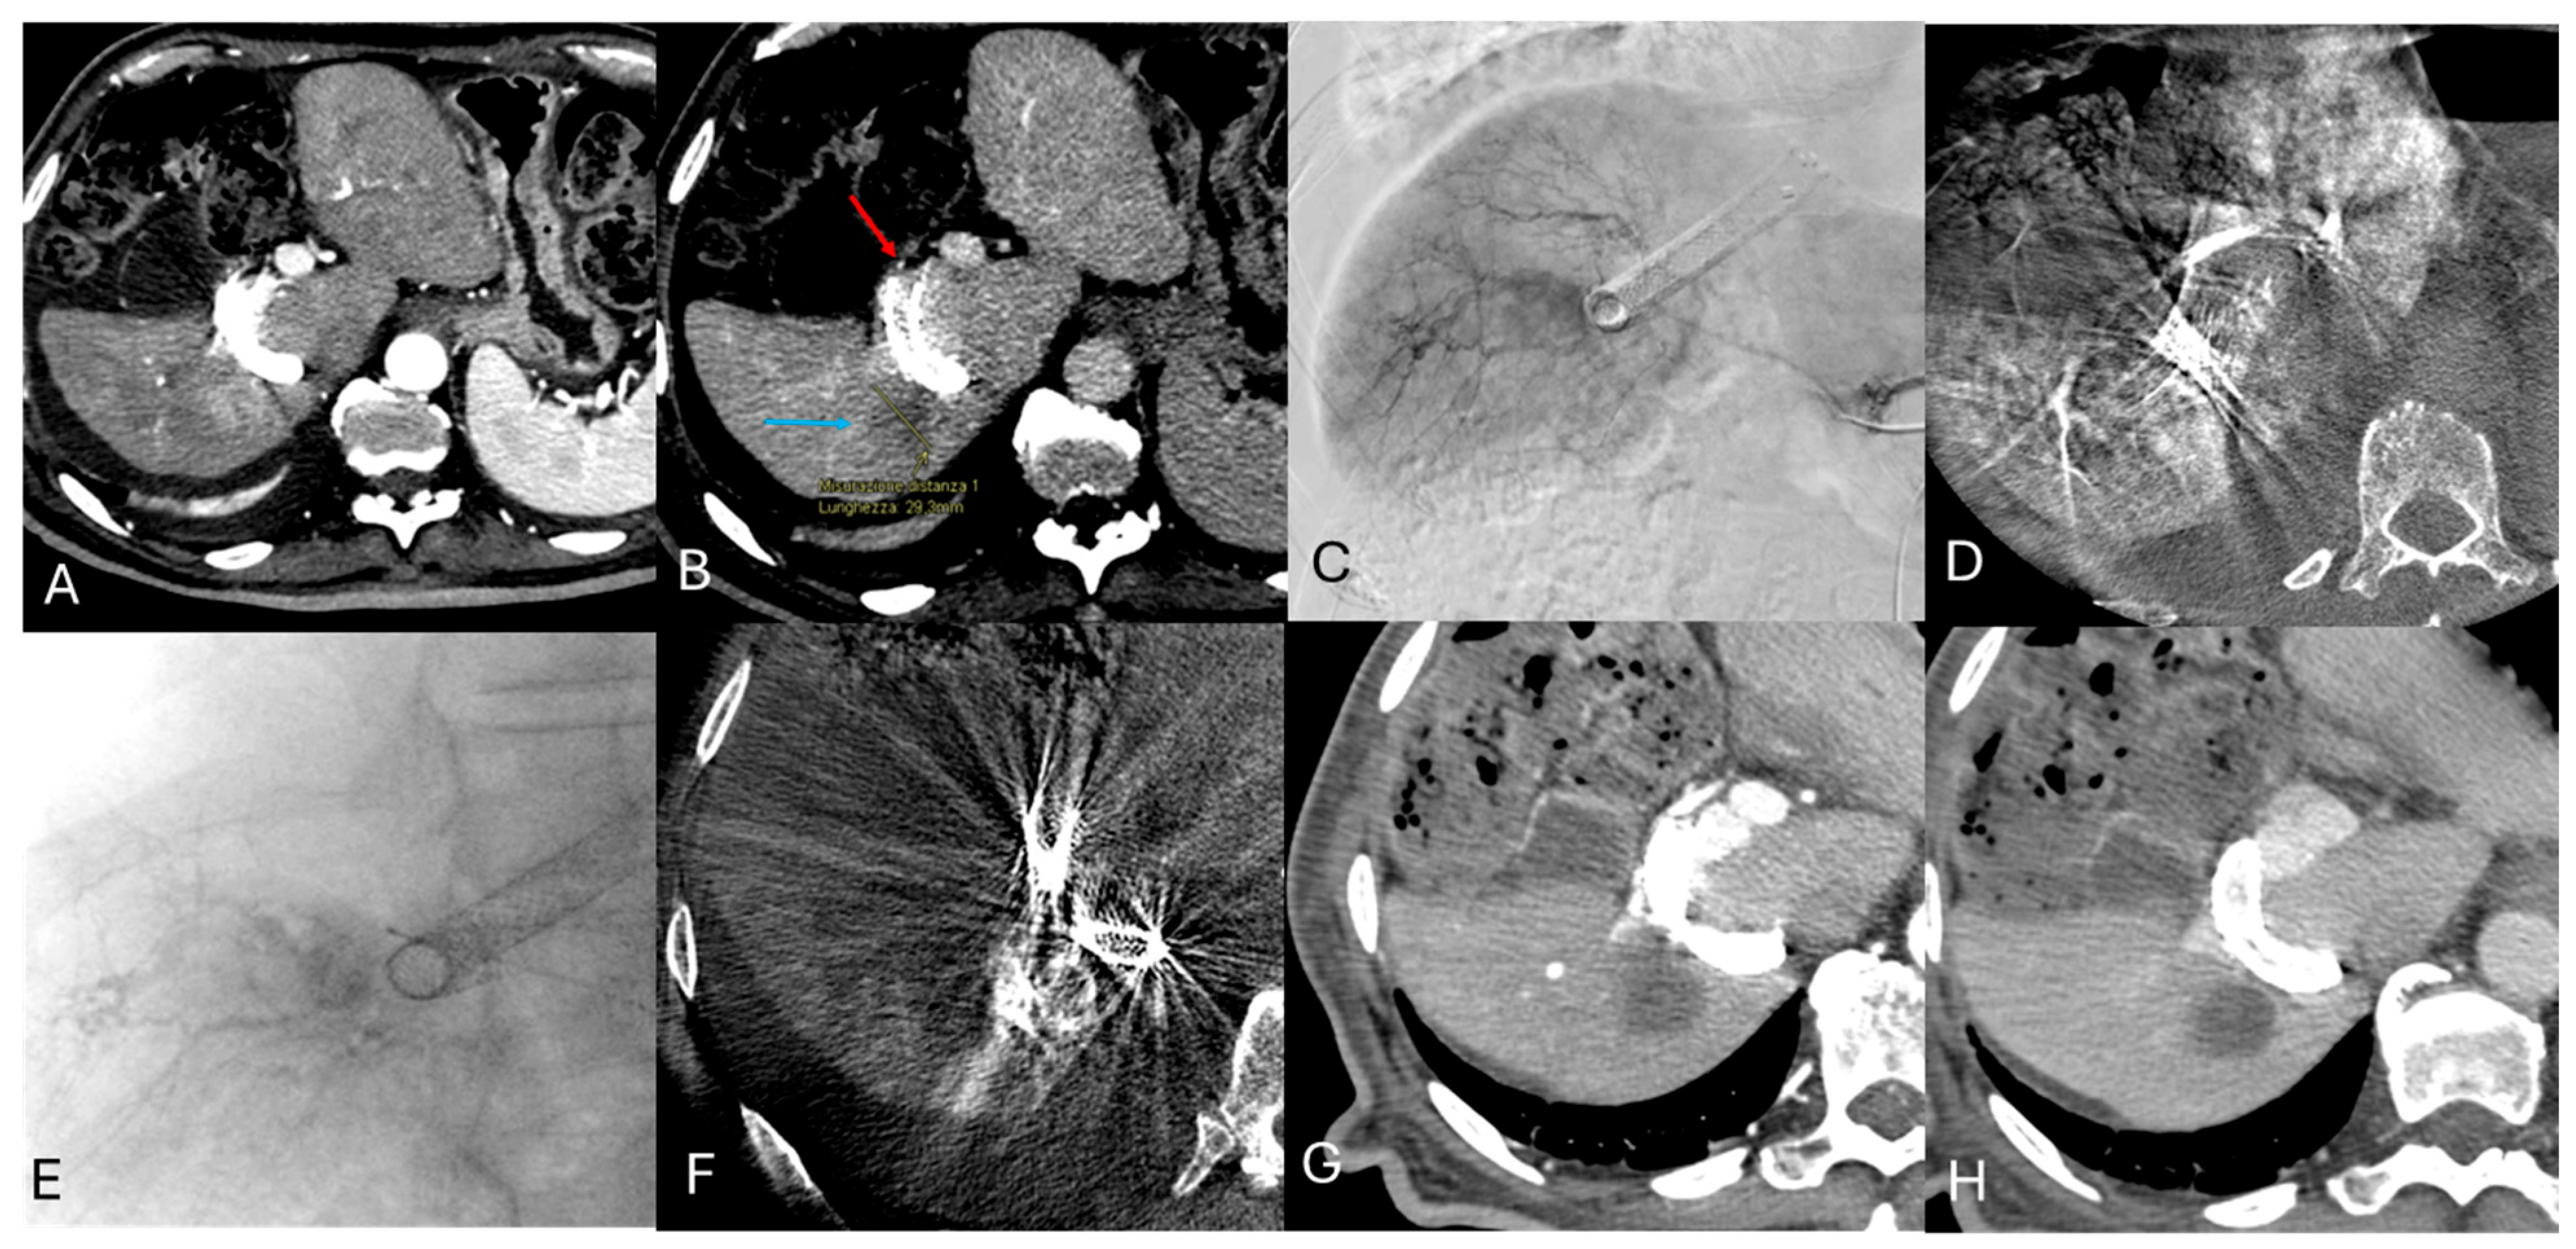

2.3. DSM-TACE Procedure